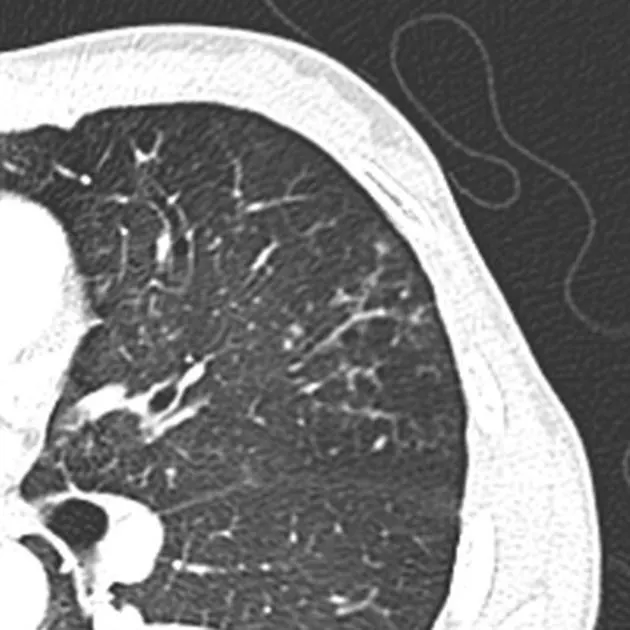

3) endobronchial spread

•

경계가 분명한 2~4 mm 크기의 nodules 또는 branching

Tree-in-bud sign : 의미. 흔함.